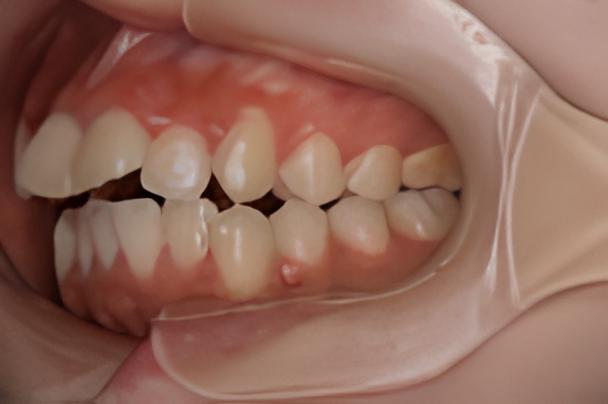

術前と術後の変化

お口全体の変化